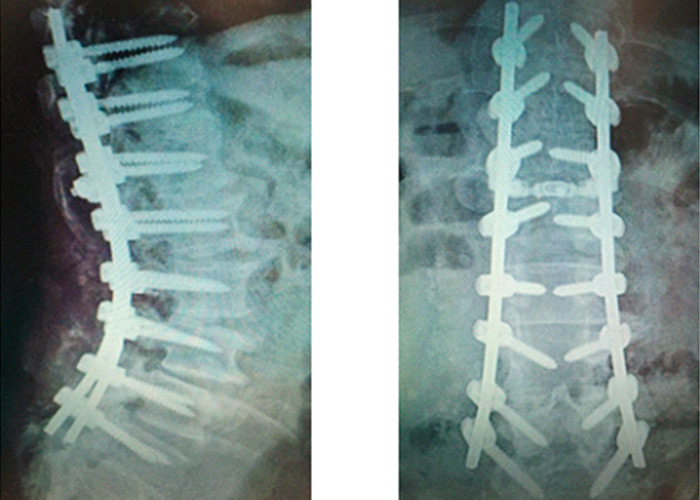

Preoperatorio

cirugia-de-columna-en-madrid-instituto-cac

preoperatorio-cirugia-de-columna-vertebral-en-madrid